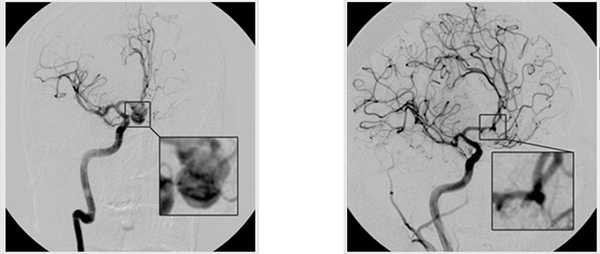

В статье освещен опыт использования двустороннего супраорбитального keyhole-доступа для хирургического лечения множественных аневризм в рамках одной общей анестезии. Описанный авторами опыт, несомненно, является уникальным, полезным и малоизученным на территории нашей страны ввиду малого распространения keyhole-доступов к аневризмам вообще, и в частности редкого использования двусторонних keyhole-доступов.

Научная и практическая новизна описанного метода заключается в том, что авторы использовали малоинвазивное хирургическое лечение для множественных аневризм, получив в результате не только радикальность выключения обеих аневризм из кровотока, но и отличный косметический результат.

В случае зеркальных аневризм средних мозговых артерий возможно использование последовательного клипирования каждой аневризмы. При этом оперативное лечение разбивается на этапы, разделенные несколькими сутками или даже больше. В части случаев используется комбинация микрохирургического и эндоваскулярного лечения аневризмы. Общеизвестно, что в отличие от микрохирургического метода лечения аневризм средней мозговой артерии при эндоваскулярном методе хирург сталкивается с большими сложностями.

Если использовать микрохирургическое выключение аневризм средней мозговой артерии из кровотока с применением традиционных доступов (птериональная краниотомия), то приходится применять либо весьма затруднительные контралатеральные доступы, либо две отдельные птериональные краниотомии. Отдельные краниотомии имеют весьма спорный косметический результат. Зачастую в позднем послеоперационном периоде развивается атрофия височных мышц.

Поэтому использование двустороннего супраорбитального keyhole-доступа имеет очевидное косметическое преимущество, так как разрез кожи проводится по брови и не нарушает целостности височной мышцы, а также не оставляет рубца на волосистой части головы.

Отдельного внимания заслуживает быстрота выполнения оперативного вмешательства через keyhole-доступ, в результате чего имеется возможность микрохирургического выключения аневризм через два отдельных доступа в рамках одной общей анестезии (общее время вмешательства составило 100 мин).

Статья хорошо проиллюстрирована. Имеются данные МСКТ-ангиографии до операции и после нее, позволяющие оценить радикальность клипирования аневризм. Включены интраоперационные фото, а также фотографии лица пациента после операции, позволяющие реально оценить косметический результат.